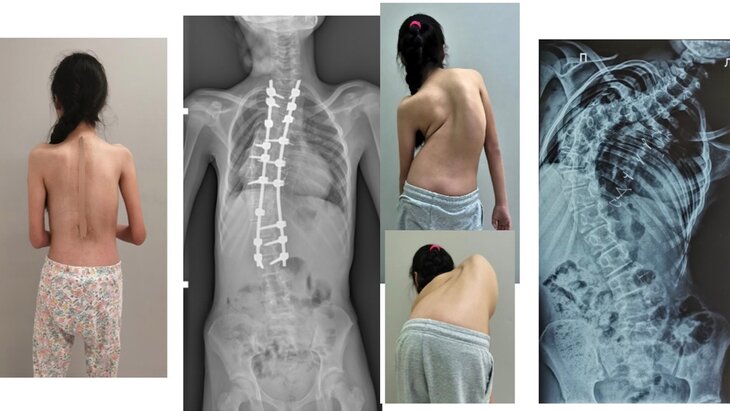

Специалисты Российской детской клинической больницы (РДКБ) провели операцию 12-летней девочке из Омска с тяжелой формой сколиоза. Об этом сообщила пресс-служба медучреждения.

Там уточнили, что угол деформации позвоночника составил 115 градусов. Как сказали врачи, сколиоз у девочки активно прогрессировал, откладывать лечение было нельзя, поскольку на фоне заболевания у ребенка также развилась сердечная недостаточность.

В пресс-службе добавили, что в момент поступления девочки в больницу ее левое плечо было на десять сантиметров ниже правого, кроме того, у нее был ярко выраженный реберный горб. Ситуация осложнялась врожденным пороком сердца и множественными ранее проведенными операциями. Но медики, подготовив тактику и план лечения, прооперировали пациентку, отметили в медучреждении.

Как рассказал кандидат медицинских наук, хирург больницы Андрей Пантелеев, в тела позвонков со второго грудного по третий поясничный специалисты поставили транспедикулярные винты, которые потом соединили между собой стержнями. Затем врачи изменили ось позвоночника в трех плоскостях, за счет чего добились коррекции. Последним этапом на протяжении металлоконструкции уложили костный аутотрансплантат, чтобы обеспечить ее максимальную стабильность в будущем, объяснил он.

В заключение он сказал, что врачи смогли устранить реберный горб и дисбаланс плечевого пояса, у ребенка улучшились функции органов грудной клетки.